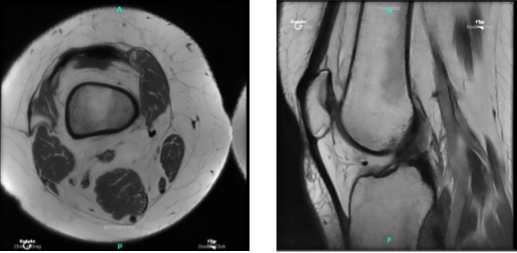

MRI Right knee non-contrast

After being involved in a car accident, a 46-year-old female patient came to visit a doctor at the office and complained of pain on the inside of her right knee. Her conventional medical care failed. A vertical radial tear of the medial meniscus of the right knee was discovered by MRI.

An examination of the medial tibiofemoral compartment revealed a vertical radial tear along the body of the medial meniscus that extended up to the capsule. The intercondylar notch examination revealed an undamaged ACL.